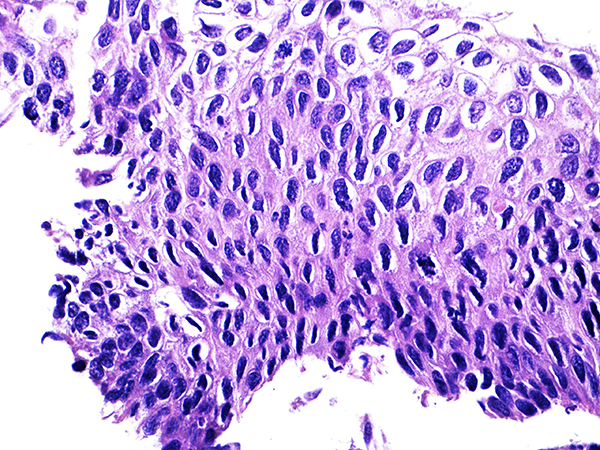

Case 4

Soft Bx CIN 3

40x - High Power |